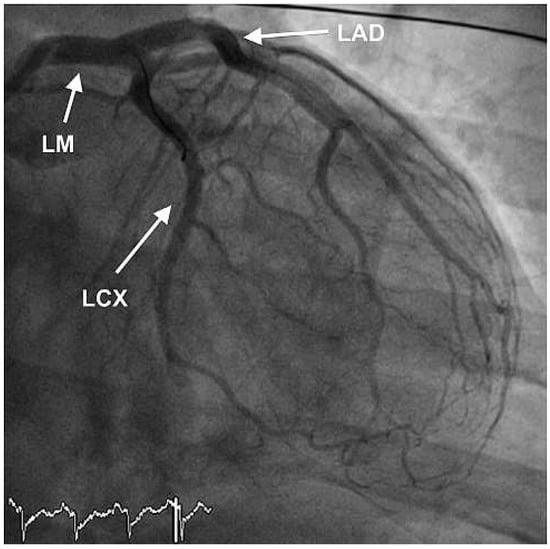

Furthermore, the right coronary artery showed a subtotal thromNo botic occlusion (Figure 3). Prior to the local treatment, a bolus of heparine 5000 IU and Abciximab were administered due to the heavy thrombus load. Thrombus aspiration was performed using an aspiration-catheter (Export AP, Medtronic) in all three coronary vessels. Due to persistent thrombotic material in the mid LAD, two low-pressure balloon inflations were done with a good end result (Figure 4 and Figure 5). There were no periprocedural complications. A treatment with life-long aspirin, one-year prasugrel, Betablocker and ACE-Inhibitor was initiated. The next day, a transesophageal echocardiography demonstrated improved LV-function (EF 50%) without evidence for an intracardiac thrombus or a patent foramen ovale (PFO).

Figure 4. RAO view showing good end result after thrombus aspiration in LAD and RCX and PTCA of the LAD.